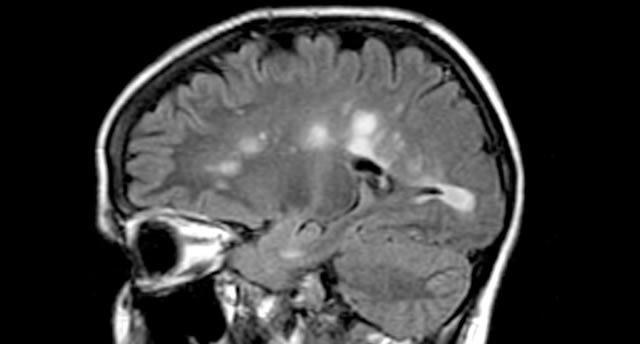

- Απεικονιστικός έλεγχος, κυρίως μαγνητική εγκεφάλου, ενδεχομένως και νωτιαίου μυελού